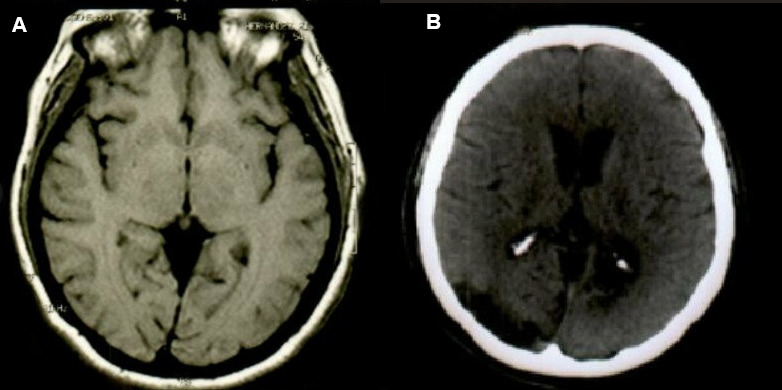

Case presentation: We report the case of a patient with multiple brain metastases, found during follow-up, after the presentation of stroke. This case stands out because the embolization causing the brain metastasis might have occurred either during the ischemic stroke or when the cardiac myxoma was being removed. In our case, the patient was evaluated during follow-up with brain magnetic resonance imaging, finding multiple metastatic lesions. To determine the type of lesion, a biopsy was performed and the histological diagnosis, which was indicative of metastatic tissue of left atrial myxoma.